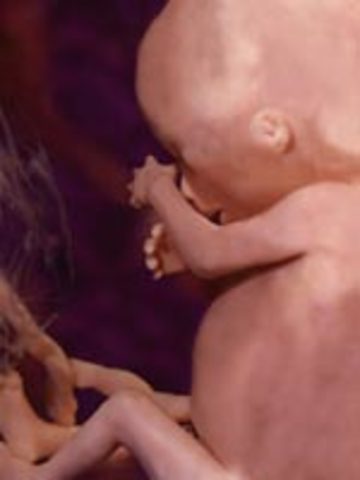

• Week 12

Week 12

Fetus is 2.5 inches, starts moving spontaneously. Face begins to look like a baby face, pancreas produces insulin, the fingernails and toenails appear, baby can suck thumb and get hiccups baby can feel pain.

• Week 13

Week 13

Fetus is 3 inches, bones replace cartilage, external genitalia is almost defined.